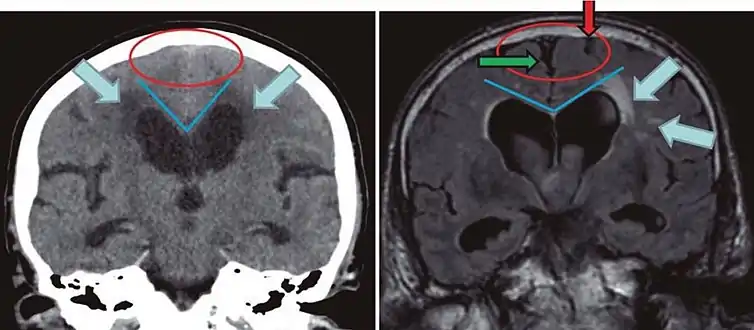

Difference from hydrocephalus

Cerebral atrophy can be hard to distinguish from hydrocephalus because both cerebral atrophy and hydrocephalus involve an increase in cerebrospinal fluid (CSF) volume. In cerebral atrophy, this increase in CSF volume comes as a result of the decrease in cortical volume. In hydrocephalus, the increase in volume happens due to the CSF itself.[20]

| ||

| Normal pressure hydrocephalus | Brain atrophy | |

|---|---|---|

| Preferable projection | Coronal plane at the level of the posterior commissure of the brain. | |

| Modality in this example | CT | MRI |

| CSF spaces over the convexity near the vertex (red ellipse | Narrowed convexity ("tight convexity") as well as medial cisterns | Widened vertex (red arrow) and medial cisterns (green arrow) |

| Callosal angle (blue V) | Acute angle | Obtuse angle |

| Most likely cause of leucoaraiosis (periventricular signal alterations, blue arrows |

Transependymal cerebrospinal fluid diapedesis | Vascular encephalopathy, in this case suggested by unilateral occurrence |